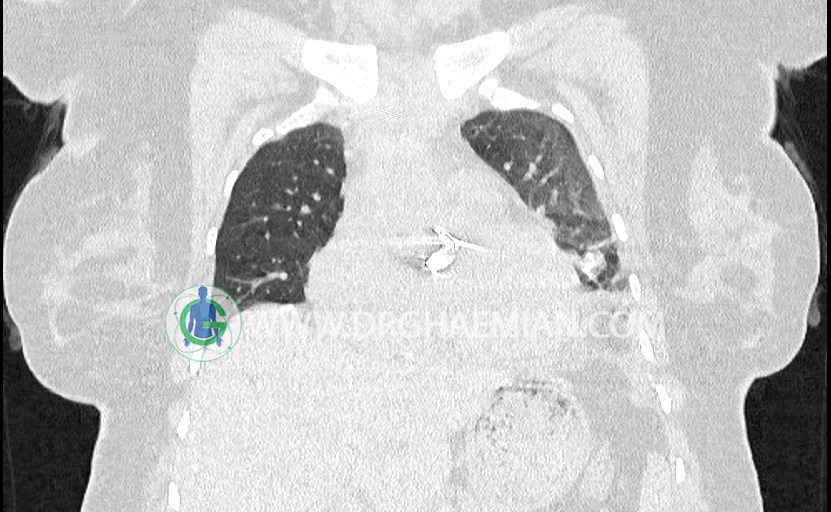

سی تی اسکن ریه یک روش تصویربرداری است که با استفاده از تششعات تصاویر عرضی مقطعی از ریه و بالا تنه ایجاد می کند. در این کیس نشانه های استرنوتومی مدیان و دریچه میترال و افیوژن پلور همراه با فروپاشی سمت چم مشاهده می شود.

در سی تی اسکن اسپيرال ريه ها و مدياستن بدون کنتراست وريدی (مولتي ديدکتور 16 با مقاطع ظريف و بازسازي کرونال):

– نشانه هاي ميداسترنوتومي و والولوپلاستي ميترال و

– pleural effusion چپ همراه با passive collapse لوب تحتاني چپ

مشهود است .